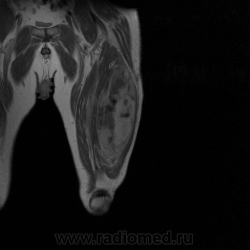

Ну вот аксиальные срезы, где то затерял =(

С учетом вашего опыта, мне кажется Вам и без дословной интерпретации МР-протокола будет все понятно.

Мой коллега в заключении указал о вероятней всего рабдолейомиосаркоме, если я ошибся то чуть позже поправлюсь.

Я тоже пока что в этом деле лось, но думаю дело поправимое, на днях улетаю С-Петербуг в МАПО(цикл КТ и МРТ), ну да ладно, что косается пациента то он ещё в 2007 году обращался по месту жительства к травматологу по поводу ушиба бедра с формированием гематомы, была назначена местная рассасывающая терапия, до 2009г. видимо ждали пока рассасется в декабре обратился к хирургу по поводу посинения и увеличения в объёме задней поверхности бедра, назначен гепарин в феврале был вскрыт абсцесс в этом месте, далее только в марте сподхватились по УЗИ-мягких тканей признаки образования, ну и открытая ножевая биопсия: Описание изменений, выявленных при микроскопическом исследовании: в материале фрагменты опухоли, представленной пучками вытянутых клеток с полиморфными гиперхромными, местами уродливыми ядрами. Определяется значительное количество митозов, встречаются поля некроза опухоли. При иммуногистохимическом исследовании опухолевые клетки экспрессируют виментин, отсутствует реакция на десмин, гладко-мышечный актин, S100. Патоморфологическое заключение: саркома мягких тканей, боее вероятно фибросаркома.